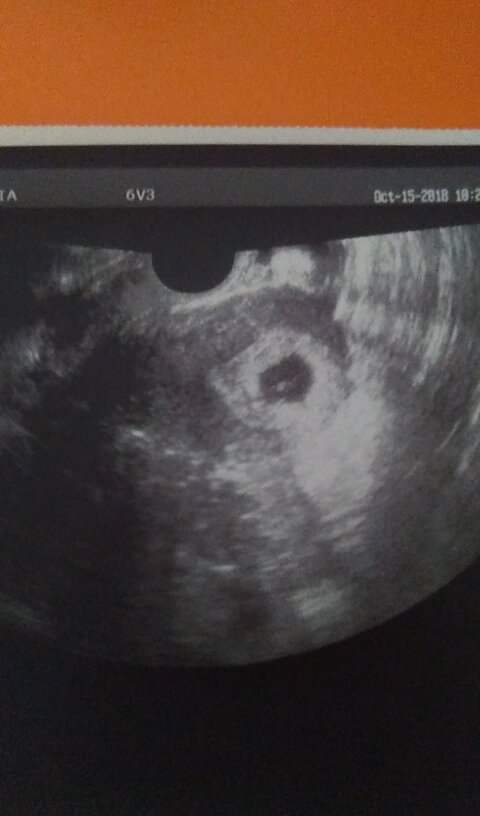

Cześć dziewczyny. Wczorajsze usg potwierdziło ciążę :D tętno było widać, ale serduszko usłyszę w przyszły poniedziałek :) wszystkim staraczkom życzę żeby się udało, a wierzę że się uda, może nie od razu ale w końcu się uda :biggrin2:

Zobacz załącznik 907916